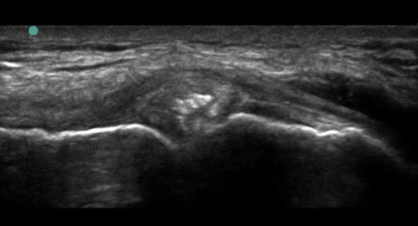

Knee Medial Meniscus Extrusion Image